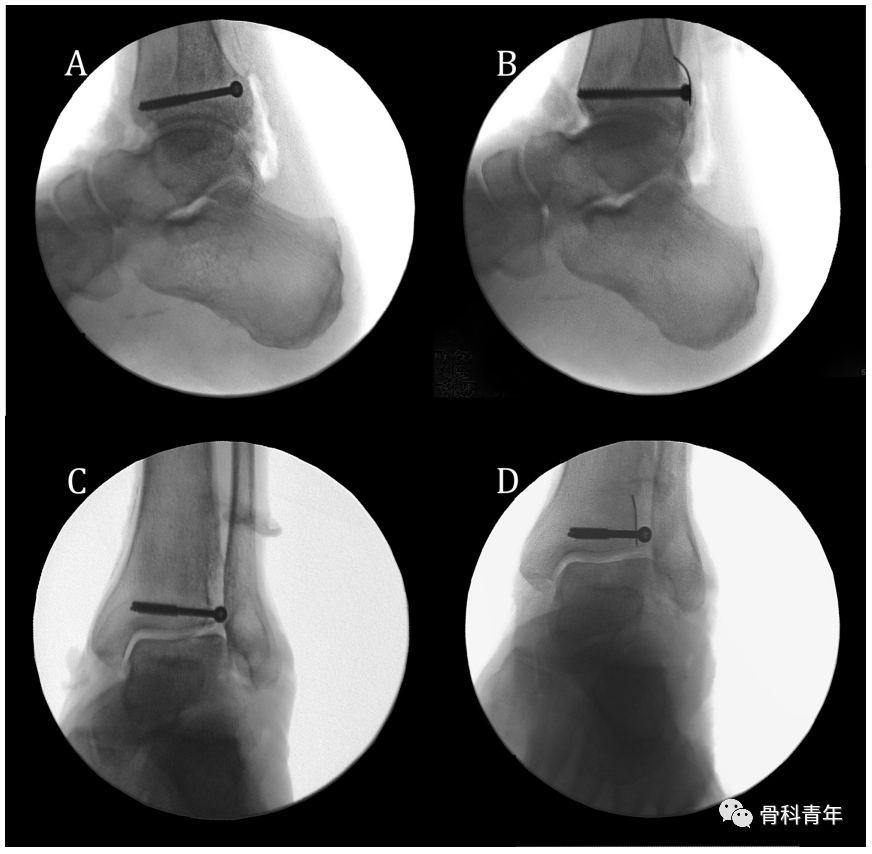

文章首先定义踝穴位上PVSL(Posteromedial vertical syndesmotic line)线,该线为在踝穴位上,下胫腓间隙中胫骨后内侧皮质缘从后向前过渡的投影线。

▲ 图示PVSL线与其在透视下的影像。

为了确定PVSL线是否可代表下胫腓间隙的内侧缘,研究者通过在下胫腓间隙内侧缘放置显影标识,并在该标识的内侧与外侧放置标识,以明确PVSL线是否易于辨别。

该例后踝螺钉穿入下胫腓的标本在CT横断中可明确。